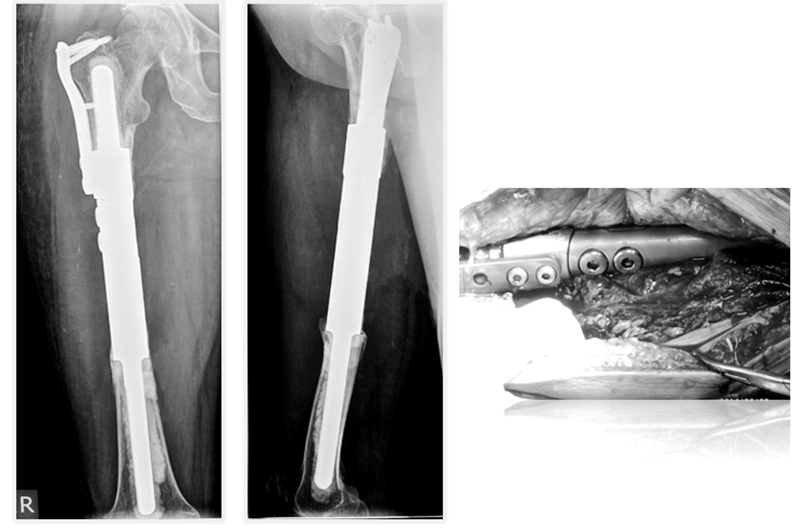

为进一步解决骨干肿瘤诊治中的难题,胡永成教授通过多年临床研究,终于设计出“骨干组配式假体”,该技术通过较小的创伤便可使患者得到好的治疗效果。除此之外,胡永成教授还根据骨干肿瘤发病部位的不同进行分区,根据不同的损伤部位可以进行个性化假体的选择,不仅可以帮助患者保留关节,患者术后还能即刻下地,大大减轻了肿瘤患者的痛苦,并提高了生存质量。

患者女性,68岁,乳腺癌病史,右股骨中段病理性骨折,股骨长段溶骨性破坏,并有跳跃病灶。病变的长度为16cm,病灶近端在小转移水平,因为近端髓腔柄较短,故选择A区骨干假体。经病理诊断为转移性腺癌,术后2周患者拆线后即可离床活动。

术后资料